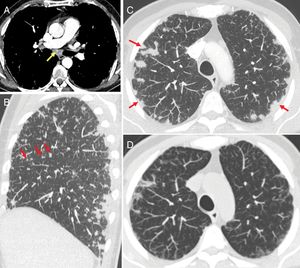

Four main patterns of CT findings have been described in immunotherapy-associated pneumonitis, following the American Thoracic Society/European Respiratory Society classification of interstitial pneumonia: cryptogenic organising pneumonia (COP), non-specific interstitial pneumonia (NSIP), hypersensitivity pneumonitis and acute interstitial pneumonia or acute respiratory distress syndrome (ARDS).39 The lower lobes are usually the most affected. Ground glass opacity is seen in virtually all cases, and a reticular pattern and consolidation in many40 (Fig. 9).

Figure 9.66-year-old man treated with nivolumab. (A) Chest X-ray pre-treatment with immunotherapy shows radiotherapy-related changes in the right lower lobe (RLL). (B) After 10 months of treatment, chest X-ray shows increases in density in both lower lung fields not seen on the previous X-ray. Computed tomography (B′) identifies ground glass areas associated with lung consolidation in the middle lobe, RLL and left lower lobe, compatible with nivolumab-induced pneumonitis. Corticosteroid treatment was given. (C) Chest X-ray performed one month later, in which radiological improvement can be seen.

Sarcoidosis-like reaction: this type of reaction can involve lymphadenopathy, in which case mediastinal and hilar lymphadenopathy may be seen, or involve the lungs, where nodules with a mainly perilymphatic distribution pattern can be identified39 (Fig. 10). It is very important to take sarcoidosis-like reaction into account when conducting a follow-up study on a cancer patient which includes chest CT, as this AE should not be confused with metastatic progression.

Figure 10.A 54-year-old male with advanced renal cell carcinoma treated with nivolumab and ipilimumab combined therapy, whose images show a sarcoidosis-like pattern. (A) Chest computed tomography (CT) with mediastinal window shows mediastinal lymphadenopathy (an enlarged subcarinal node indicated with arrow). (B and C) The CT scan shows nodular images of a perilymphatic distribution pattern (arrows in the sagittal reconstruction) and pleural-based peripheral consolidation (arrows in the axial reconstruction). (D) Axial CT scan in the same patient after 2 weeks of corticosteroid treatment which shows radiological improvement.